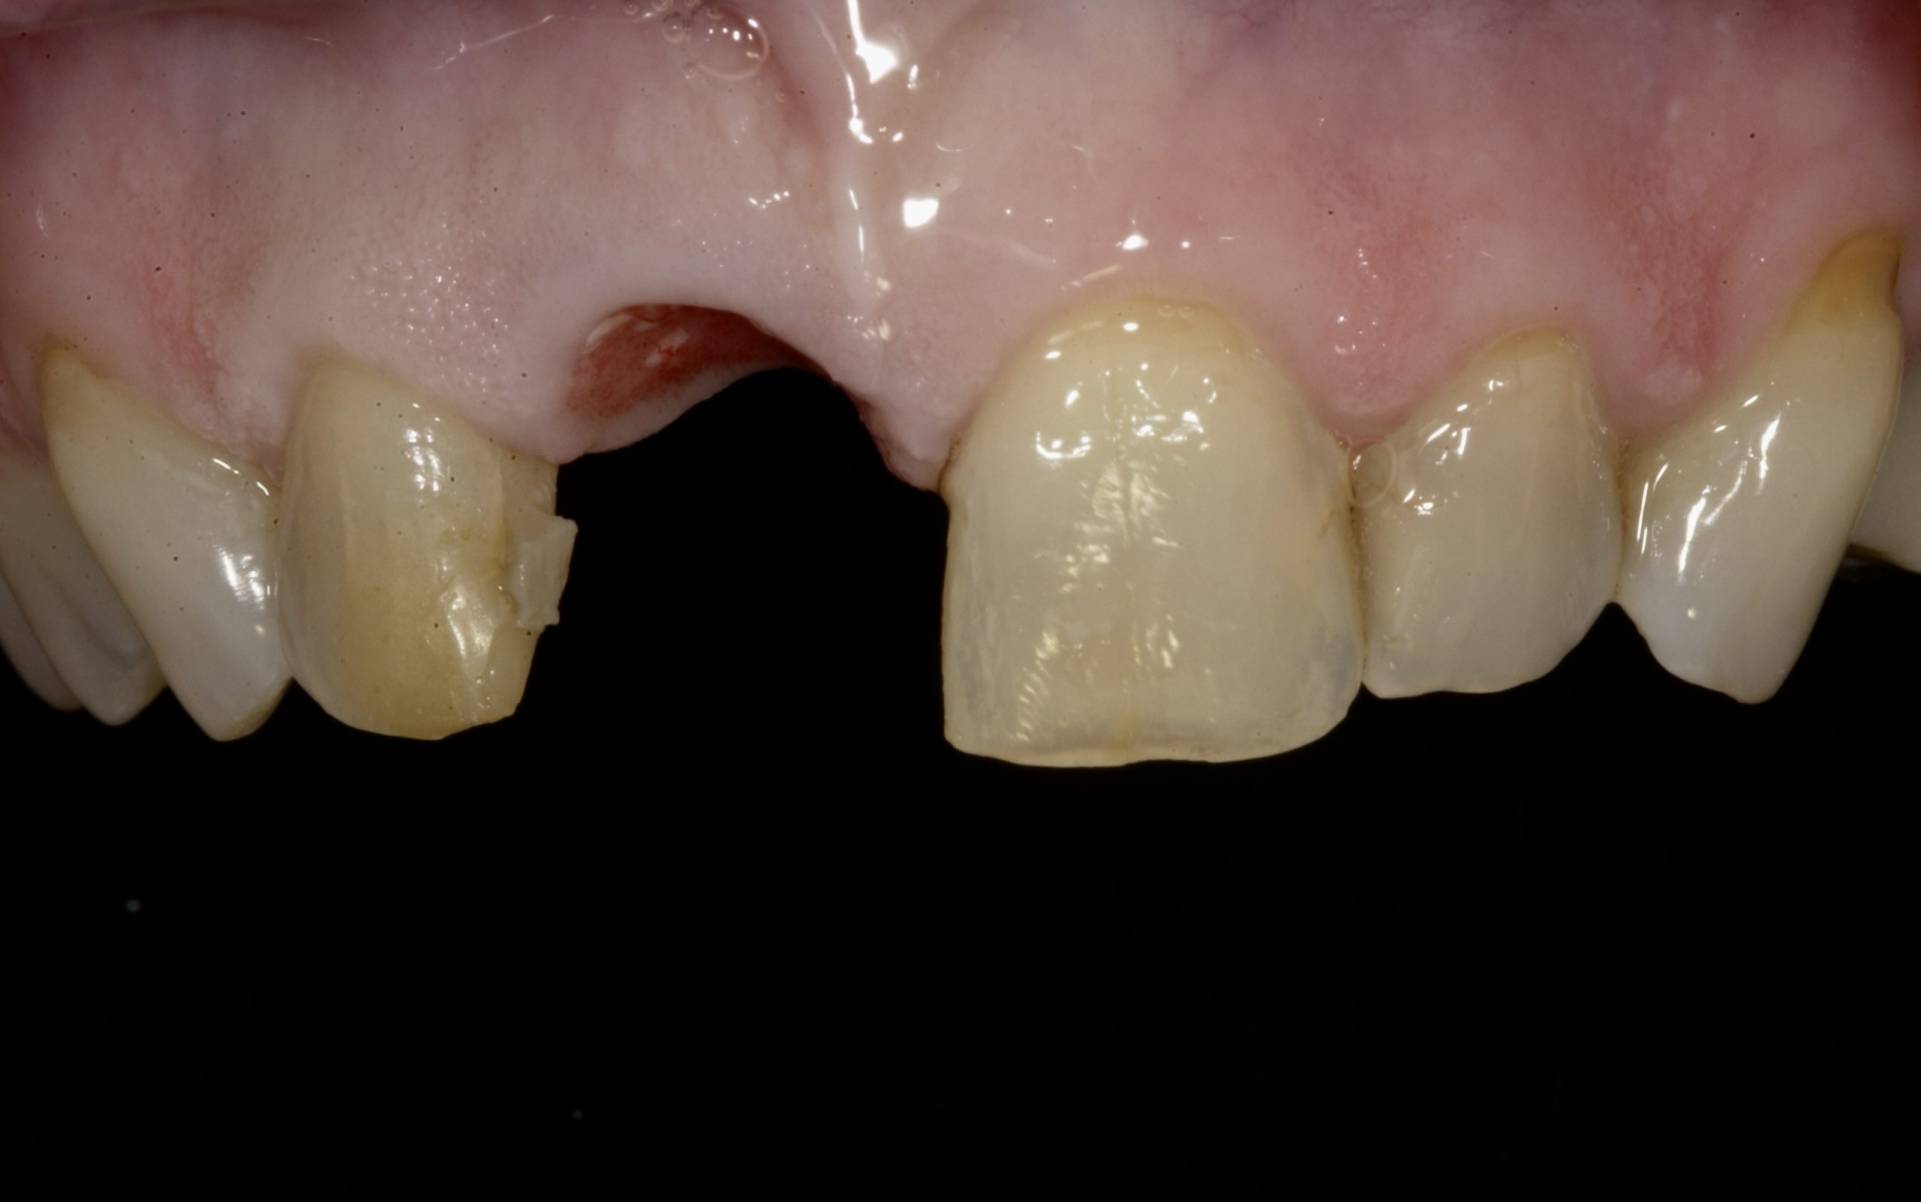

Ein Implantat trägt nicht nur zur Wiederherstellung von Kaufunktion und Ästhetik bei, sondern schützt auch den Kieferknochen vor Abbauprozessen, die nach Zahnverlust auftreten können. Voraussetzung für den langfristigen Erfolg ist eine sorgfältige Planung unter Berücksichtigung von Knochenangebot, Weichgewebe, Funktion und individueller Belastung.

Mithilfe moderner Diagnostik, mikrochirurgischer Techniken und gewebeschonender Verfahren schaffen wir optimale Voraussetzungen für eine sichere Einheilung. Bei Bedarf werden knochenaufbauende Maßnahmen und biologische Regenerationskonzepte integriert, um auch in anspruchsvollen Situationen stabile Ergebnisse zu erzielen.